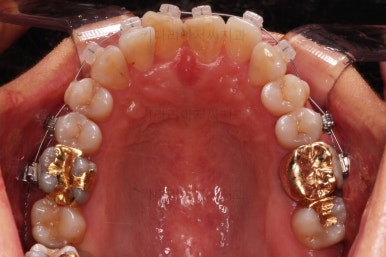

동래임플란트교정 마무리 되었습니다.

임플란트 머리도 잘 올라갔고, 치열도 가지런해졌으며 교합이나 중앙선도 적절히 마무리 되었습니다.

전후 비교를 해보겠습니다.

웃는 모습이 매우 우아해지셨어요.

미소가 굉장히 예뻐지셨습니다.

더군다나 예상한대로 발치교정으로 입을 많이 넣었음에도 팔자주름이나 피부처짐이 없이 잘 마무리 되었습니다.